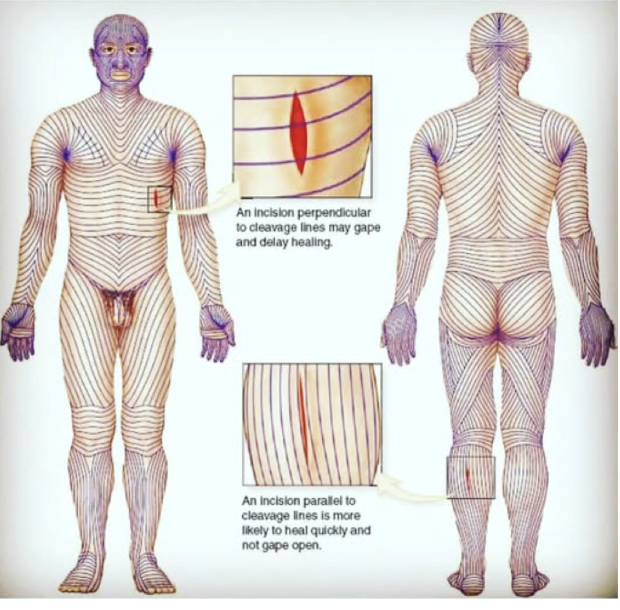

Langer’s lines

cleavage lines, are topological lines drawn on a map of the human body parallel to the natural orientation of collagen fibers in the dermis

-generally perpendicular to underlying muscle fibers, prevents gaping, allows for better cosmesis